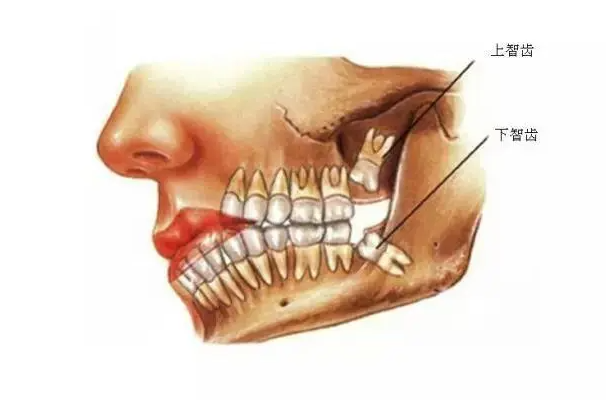

智齿是恒牙里长得最晚的牙齿,它通常会在18到25岁之间的时间长出来,一般女孩子比男孩子的智齿长出的时间要早一些,也有些人不会长出这种牙齿。智齿通常都长在口腔的最里边,有四颗,它们分别一一对应。智齿又被叫做第三磨牙,在第二磨牙的旁边,是早期人类为了更好的咀嚼而长出来的一个牙齿。

因为原始时代人类经常会吃一些难以咀嚼的东西,原先的牙齿也不太够用,所以发展出第三磨牙,但是由于现代人们的吃食越来越精细了,不需要过度的咀嚼,因此原先的智齿就逐渐变得多余了起来,并且许多现代人的口腔中并没有给智齿留下位置,因此有些人一旦长出智齿就会挤压其他牙齿的位置,变得疼痛,这就是阻生智齿。